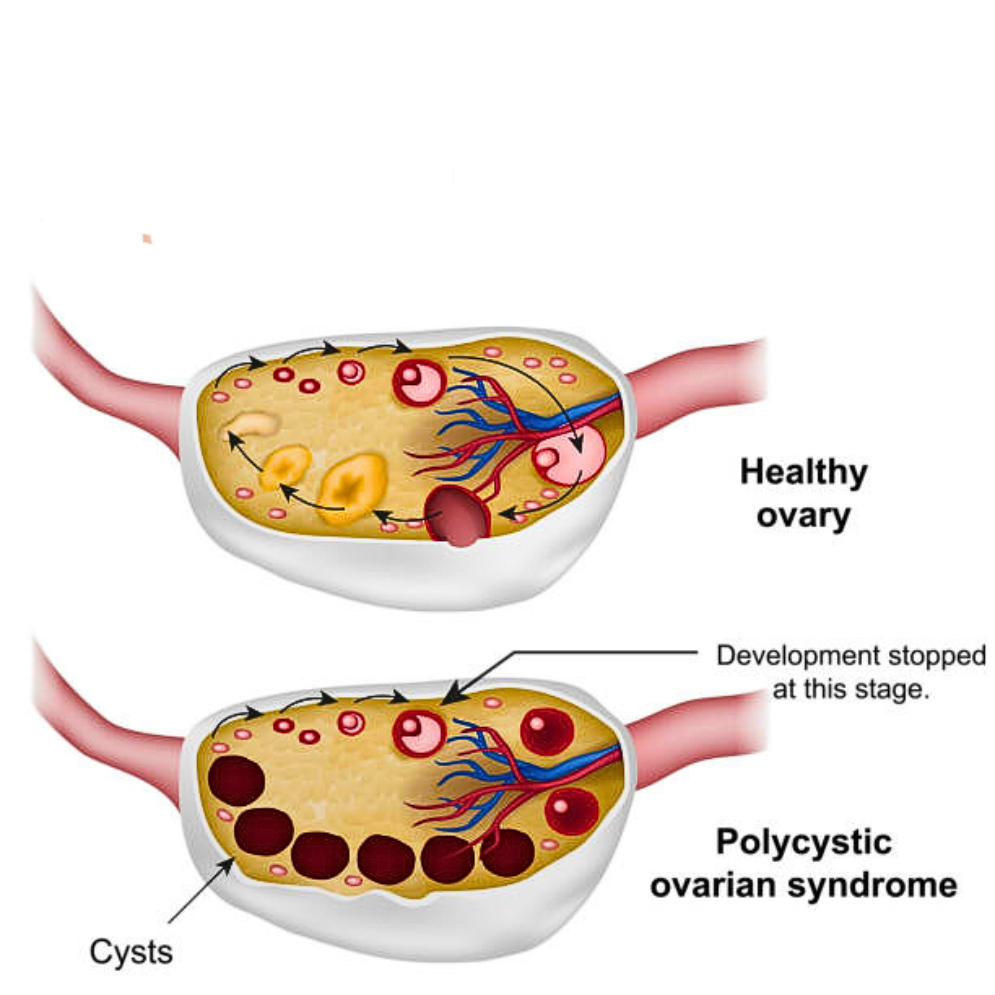

cysts & pcod